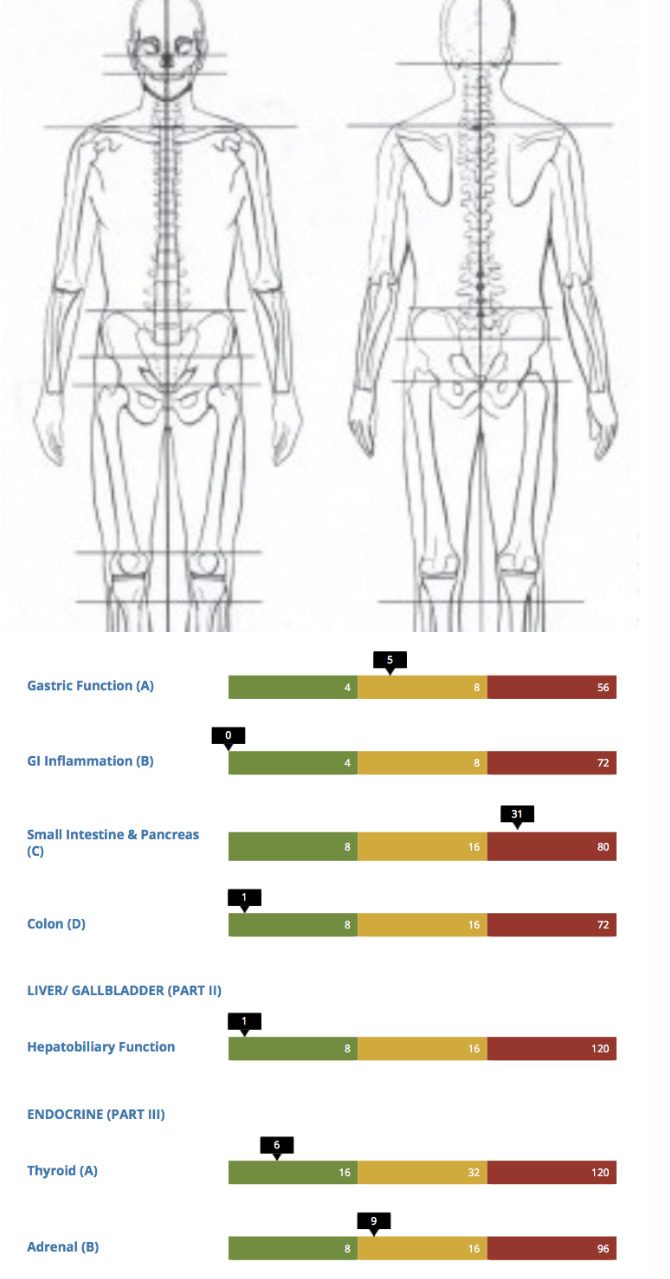

- Digestion

- Hormones

- Current endocrine health

- Current visceral health & vitality

And then we wonder why so many women are experiencing chronic pain, incontinence, sexual dysfunction, early menopause, depression, anxiety, thyroid disorders, irregular periods, chronic fatigue and inability to lose weight!! (to name just a few)